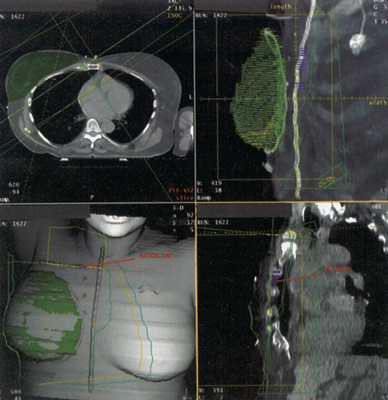

CT treatment planning virtual simulation of a patient treated with comprehensive nodal irradiation.